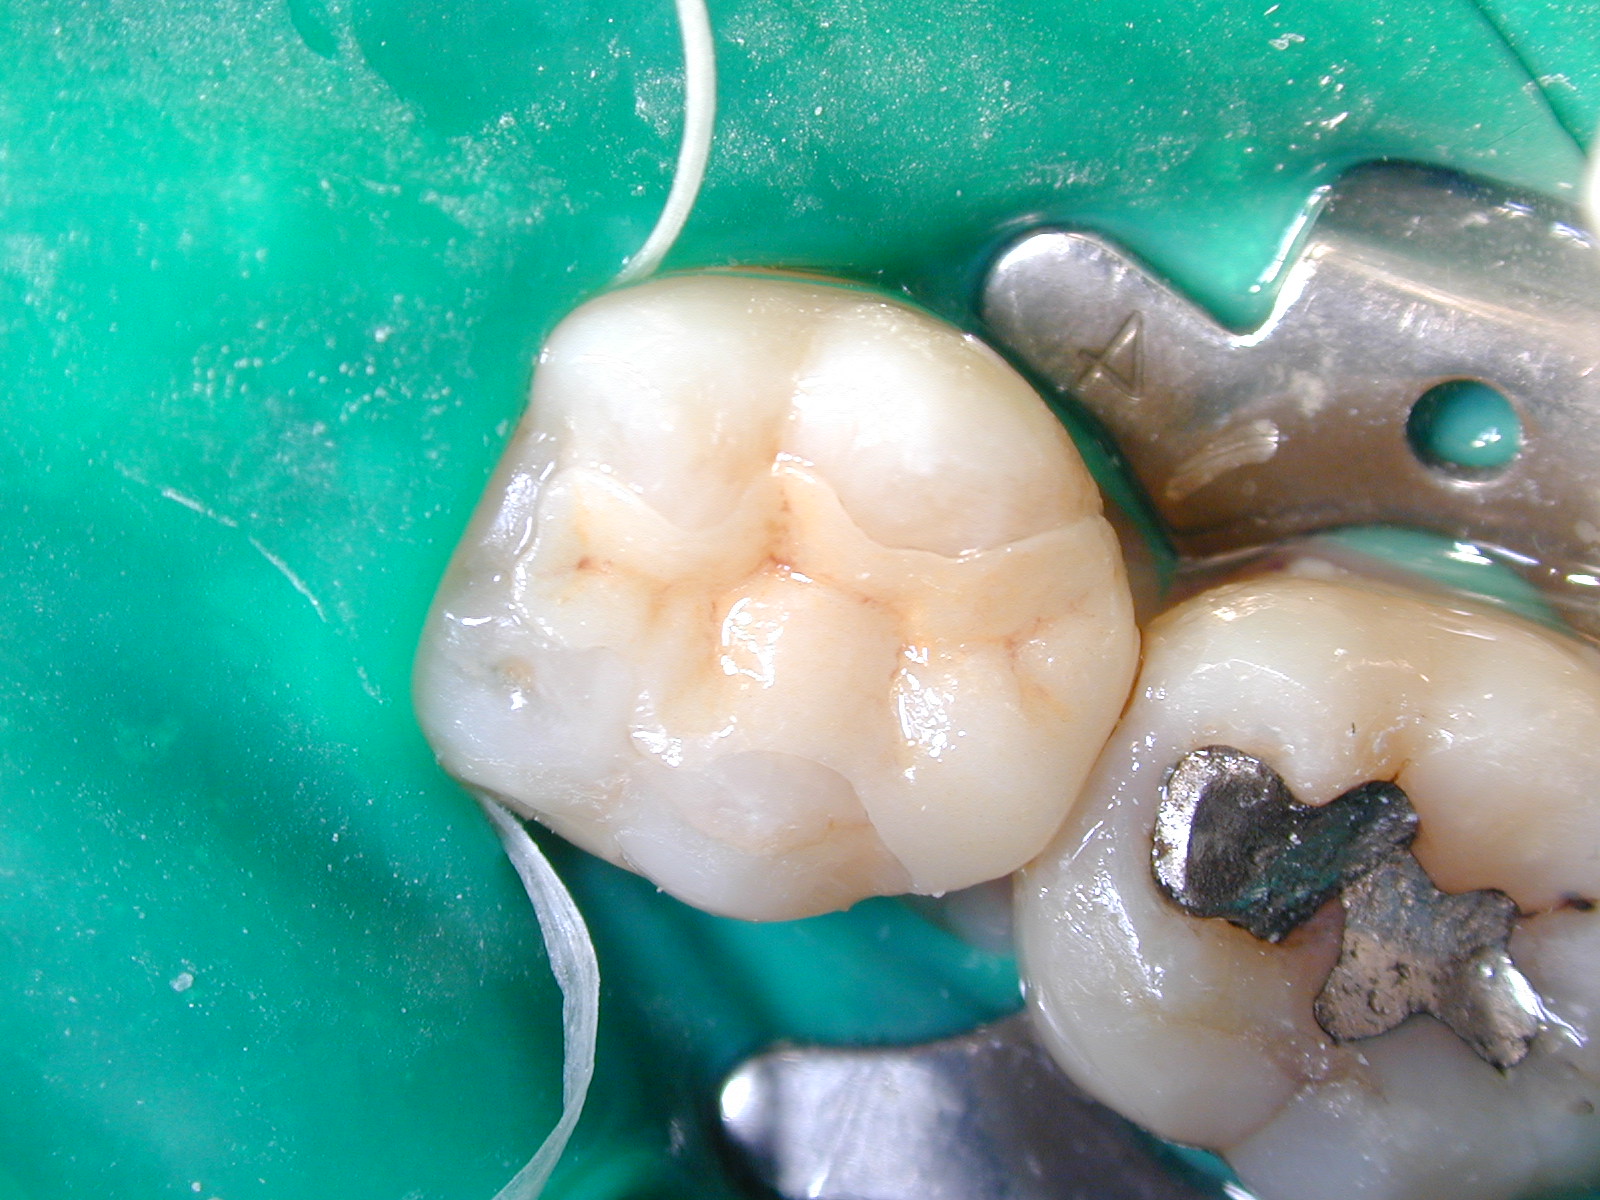

放入牙齒

用樹脂黏合劑結合傳統銀粉